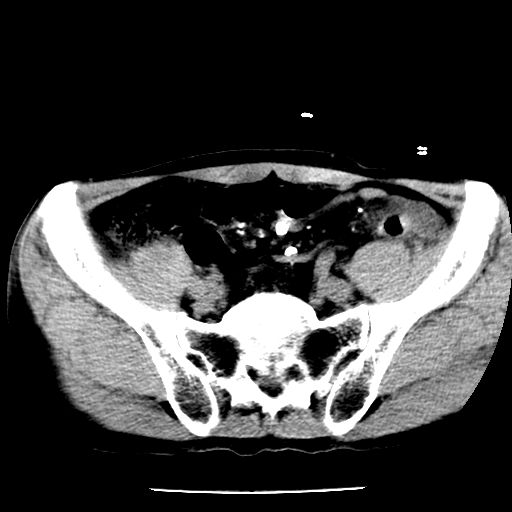

男,59岁,“结核性胸膜炎”30余年,胸部经常疼痛,多次x检查提示“肺部”炎症。腹部疼痛5日,b超提示:“肝内短管结石,余显示不清,建议进一步检查。”

两肺结核并右侧胸腔积液;脾脏、腹腔及腹膜后淋巴结结核[陈旧性];肝内胆管结石

胸部腹部都是结核(双肺。纵隔淋巴结,肝脏,脾脏,肠系膜)